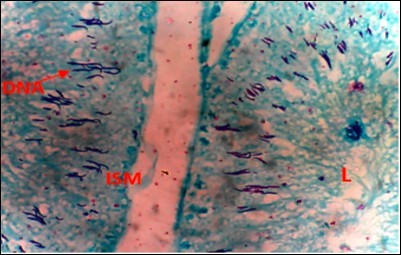

Figure 4.Diabetic Control (DC) X400 – Section of testis showing scanty DNA stained with magenta colour. DNA strands are cross linked and appear in clusters

Diabetic Control (DC) X400 – Section of testis showing scanty DNA stained with magenta colour.  DNA strands are cross linked and appear in clusters

From findings in this study, irregular and distorted arrangements of DNA in all diabetic groups (Groups B, C, D, E and F) when compared with the normal control group, may have been due to displacement of sertoli cell within the germinal epithelium of seminiferous tubules. Strands of DNA were also seen arrange in clusters in diabetic groups, showing altered and defective structure which might have resulted from base free side deletion, frame shift, cross-linking and chromosomal rearrangement. The intensity of magenta colour development in Feulgen reaction for DNA demonstration was proportional to DNA concentration. There was reduced colour intensity in all diabetic groups (Groups B, C, D, E and F) when compared with the normal control. This is in line with report from Aitken and Krausz (2001). However the degree of distortion and cross-linking of DNA strand in the group of diabetic animal models placed on high dose (1000mg/kg.bw) of A. polytricha which may be a sign of amelioration. Groups C, D and F placed on 250mg/kg.bw A. polytricha, 500mg/kg.bw A. polytricha and standard anti-diabetic drug (metformin) respectively did not show remarkable differences in terms of DNA arrangements when compared with the diabetic control group. Groups D (500mg/kg.bw A. polytricha) and group E (1000mg/kg.bw) showed visible improvement in magenta colour intensity when compared with the diabetic control group.